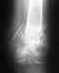

Ограничения после установки интрамедулярного штифта

Слышала,что после установки штифта в б.берцовую кость мне нельзя перегреваться,посещать сауну,солярий и меньше загорать на солнце.Объясните почему нельзя?Что случиться?